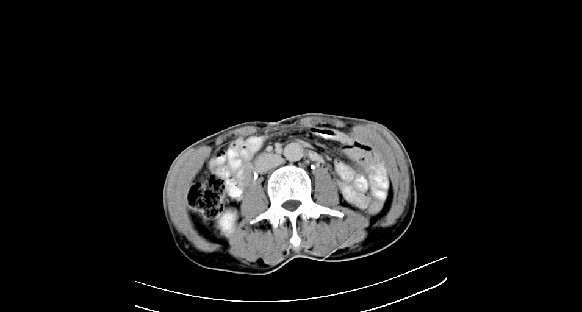

男性,70岁,体检b超发现左肾占位,请各位战友发表一下观点

左肾有两个病灶,且较大的病灶内可见点状钙化灶,增强扫描边缘也是呈渐进性强化,中央部分未见明显强化